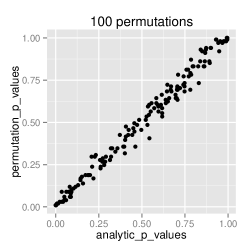

Analytical approximation of p-values

To confirm that the analytical approximation of null distribution of GDM is correct, we estimated the p-values through the approximation technique as well as through permutation testing. A range of 10 to 10,000 permutations was applied to observe the error rate. This experiment was performed on the ADNI dataset. The results displayed in figure 1 demonstrate that the analytic approximation holds with approximately error.